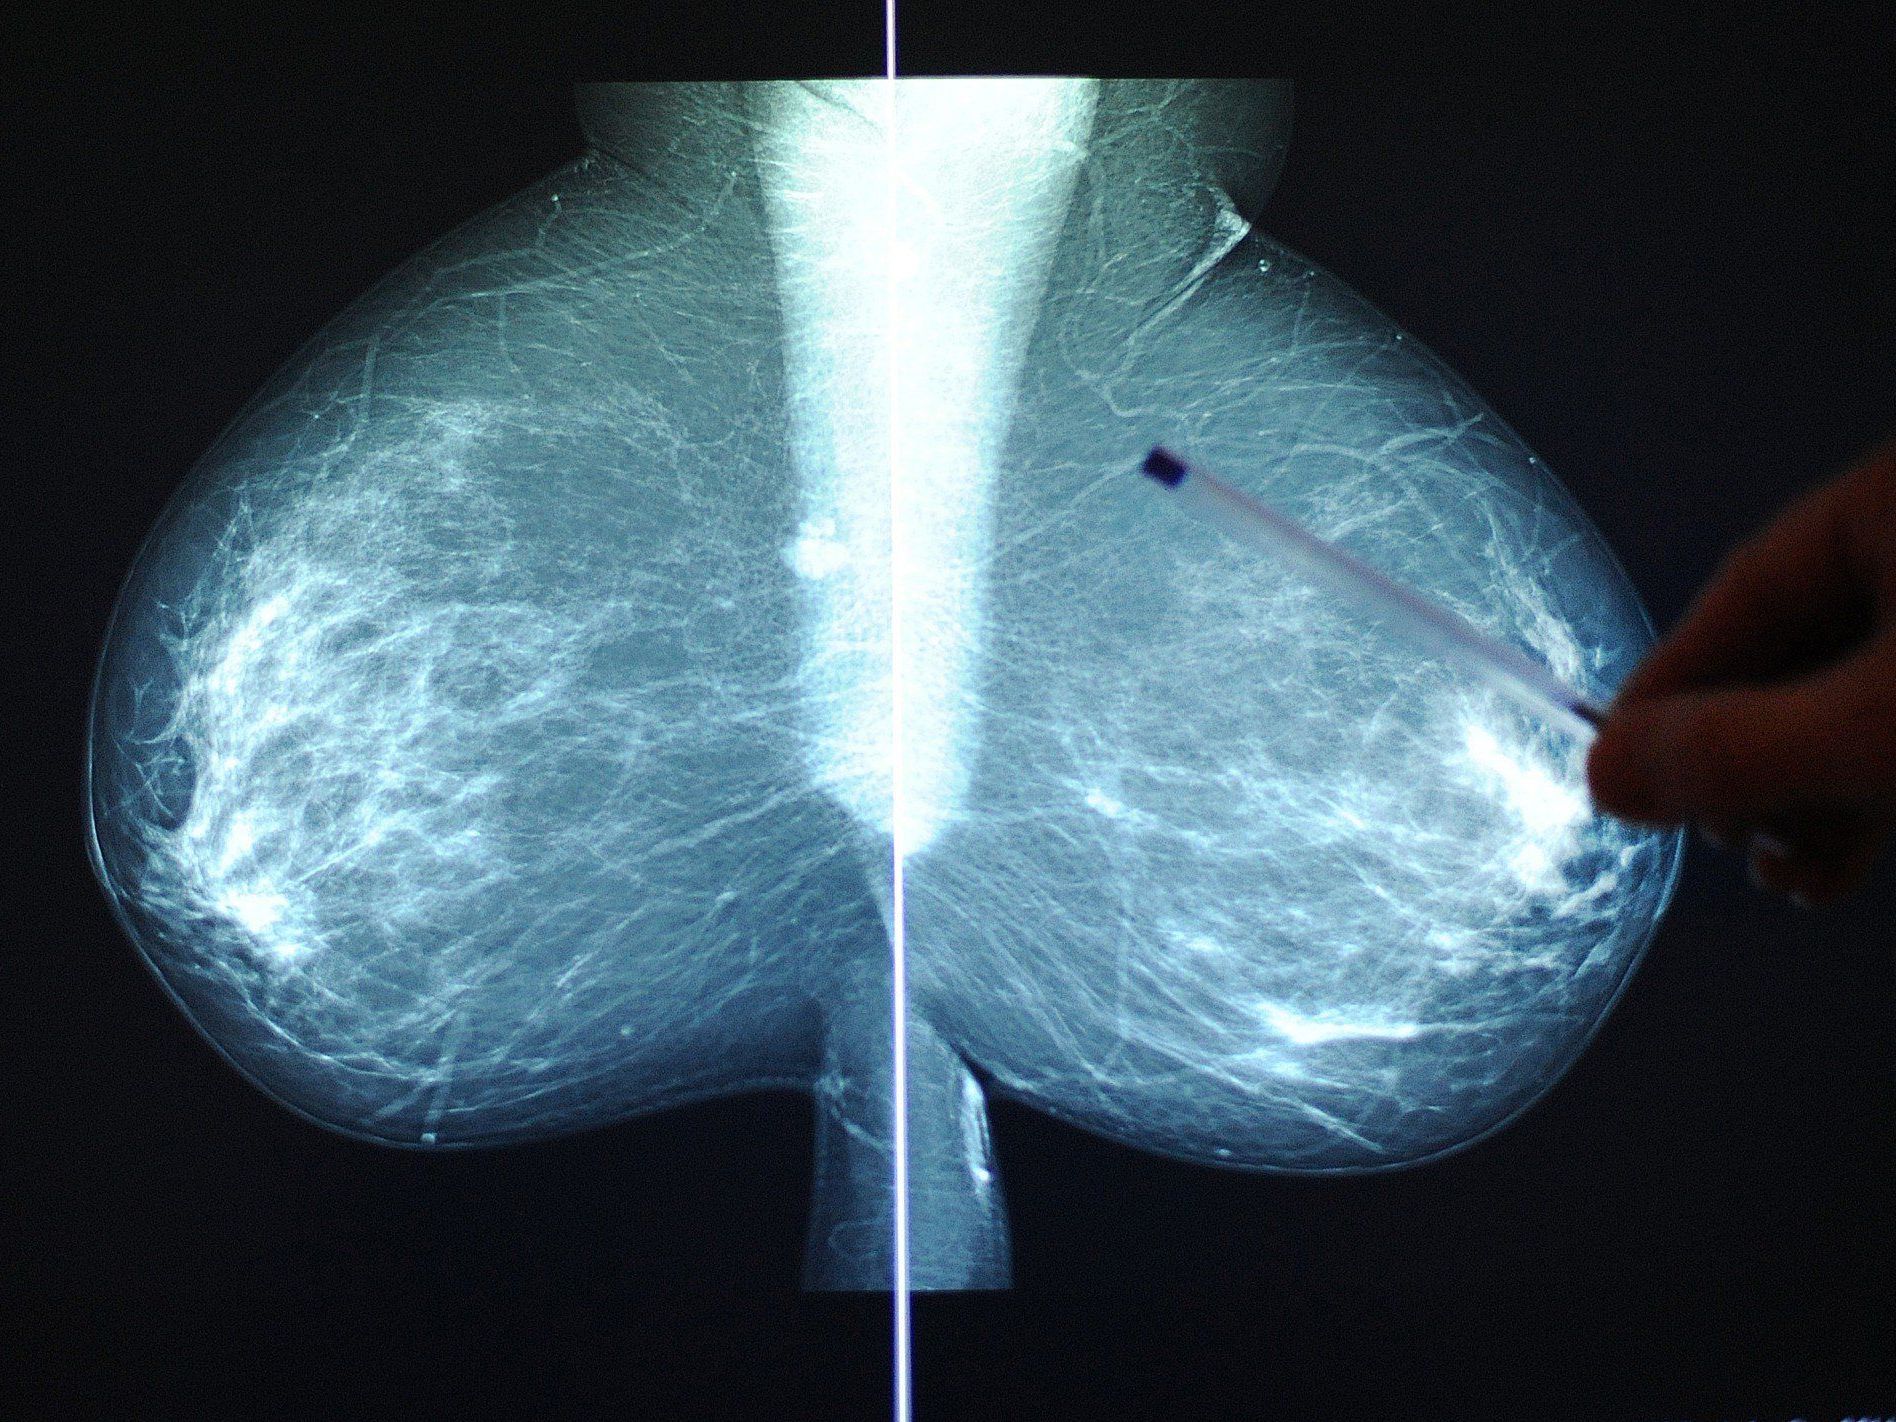

Erinnerungsschreiben - Vorziehen von Einladungen - "Opt-in" im Internet.

Erinnerungsschreiben - Vorziehen von Einladungen - "Opt-in" im Internet. ©APA

Nach Bekanntwerden von Problemen mit dem Anfang dieses Jahres in Österreich gestarteten Mammografieprogramm zur Brustkrebs-Früherkennung gibt es jetzt Änderungen an dem Projekt: Erinnerungsschreiben, Vorziehen von Einladungen, eine "Opt-in"-Möglichkeit im Internet und Visitenkarten für niedergelassene Ärzte.